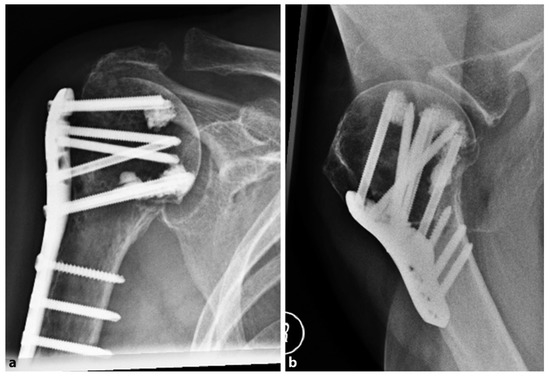

The Da Vinci system or triangular block bridge is a titanium triangle-shaped open prism, whose opposite faces are pierced and jointed with three pegs, one for each vertex (Figure 3). The triangle shape represents the evolution of the triangle-shaped bone block, which is originally handcrafted from an allograft such as iliac crest bone. The shape evolved from the beginning to the definitive version of the titanium cage (produced by Lima, San Daniele del Friuli, Italy, up to 2008 and then by Arthrex, Naples, FL, USA) [29]. Because five different sizes are available, the choice of the correct size and the exact position are therefore important. Each vertex has to fit into the head, the greater tuberosity, and the shaft, with the hypotenuse turned towards the metaphysis. This positioning ensures medial support, stopping the head from sliding down and ensuring adequate fracture support. It acts both as an expander and a metallic bridge on which it is possible to reconstruct all the fragments using minimal osteosynthesis with k-wires, cannulated screws, and trans-osseous sutures. The device aims to increase the stability in fracture with metaphyseal bone loss and to increase the proximal humeral re-vascularization and healing. That is due to stable effect obtained with the association of medial support and lateral fixation.

Figure 3. The use of a metallic cage for a proximal humeral fracture associated to plate fixation: (A) pre-operative X-ray of a displaced four-part humeral fracture-dislocation in a right shoulder; (B) The Da Vinci cage; (C) post-operative X-ray. Credit: Figure 3 from Russo et al. [40], permission conveyed through Copyright Clearance Center, Inc. (Order license ID 1027717-1).

Russo et al. retrospectively evaluated a total of 71 patients with two-, three-, and four-part proximal humerus fractures in three different case series. In 2013, they published the results of a retrospective evaluation of 69 proximal humeral fractures treated with the Da Vinci System between 2005 and 2010 [40]. In all cases, a deltopectoral approach was performed. The titanium cage was used to fill the void of the metaphysis. The fixation was performed with minimal osteosynthesis (cannulated screws or k-wires) or a low profile plate when the surgeon considered it necessary.

In almost all the cases, allograft was used to fill the cage. The choice of the associated osteosynthesis was made on the basis of the type of fracture. In all cases, minimum follow up was 2 years (range of 24–72 months). The fractures were radiographically proven to heal in 68 of 69 patients. There were two cases of malunion (one greater tuberosities dislocation, the other was a varus malposition of the head), and five patients suffered partial AVN. Because one patient suffered a deep infection, the device was removed and the patient was treated with a cemented antibiotic spacer. At the final follow up, the mean constant score was 80.25. Later, in 2017, the authors updated the series with a longer follow-up, comparing the results obtained with The Da Vinci System to the augmentation with autograft tricortical iliac crest or hand-shaped bone bank block [41]. In both groups, good clinical and radiographic results were reported, with a very low rate of complication and no statistically significant differences.